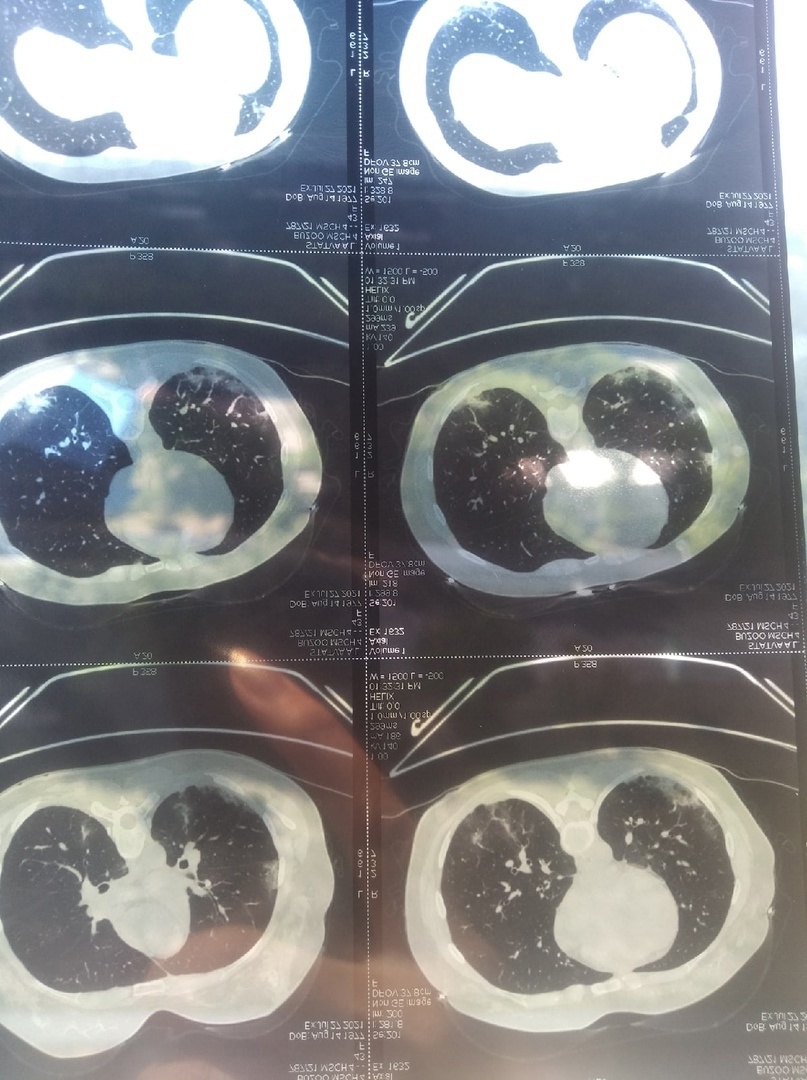

Омск область коронавирус